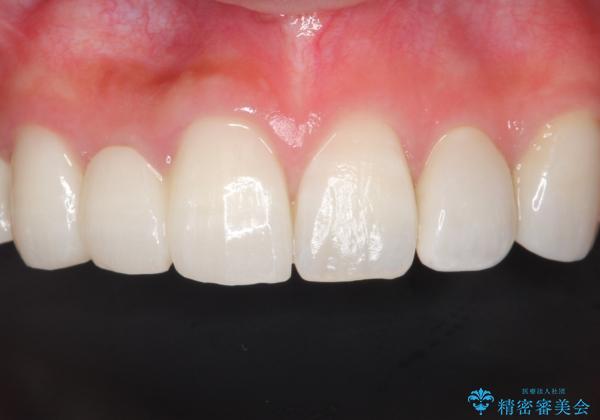

- 保険治療で装着されたかぶせ物と詰め物を変更したいとのことで来院されました。

自然なオールセラミックへ変更することとなりました。

金属を使わないセラミックへ変更することで、自然な見た目になるとともに、ぴったりとした精度の高いかぶせ物を装着することができました。